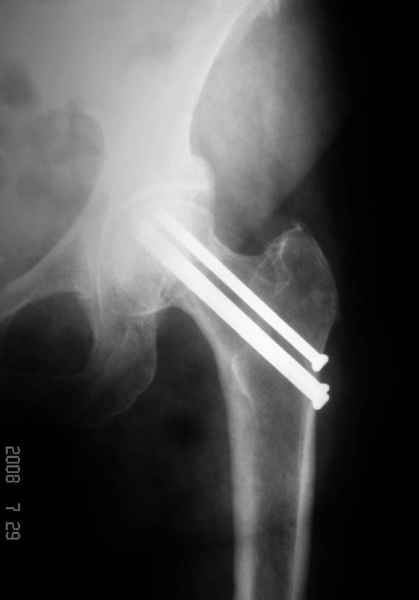

77 летняя больная направлена в нашу клинику на дальнейшее лечение. Из истории, травму получила в сентябре 2007 года и по поводу перелома шейки бедра больная была проперирована тремя каннюлированными шурупами с явным нарушением технологии установки шурупов. Внизу вместо одного шурупа имеется два, что привело к стрессу латерального кортекса. Через месяц по поводу ятрогенного подвертельного перелома сделана фиксация длинной Гамма 3. Установлен без проксимальной блокировки? (set screw). В данный момент имеется несостоятельность конструкции и ложный сустав. Передвигается с помошью костылей, конечность укорочена на 2 см. Какие будут рекомендации?Djoldas Kuldjanov, MDDepartment of Orthopedic SurgerySt. Louis University Medical Center

Где рентгенограммы, доказывающие перелом латерального кортекса из-за "неправильно установленных канюлированных винтов"

Лично я вижу интромедуллярный блокирующий остеосинтез бедренным фиксатором, с рассверливанием ретроградного отверстия под шеечный винт гамма и, как следствие, последующим переломом фиксатора, с последующим его забиванием, приведшим к угловой деформации дистальных фиксаторов и ятрогенному подвертельному перелому бедра и попыткой обвинить доктора, прооперировавшего субкапитальный перелом шейки 3мя винтами и достигшего консолидации.